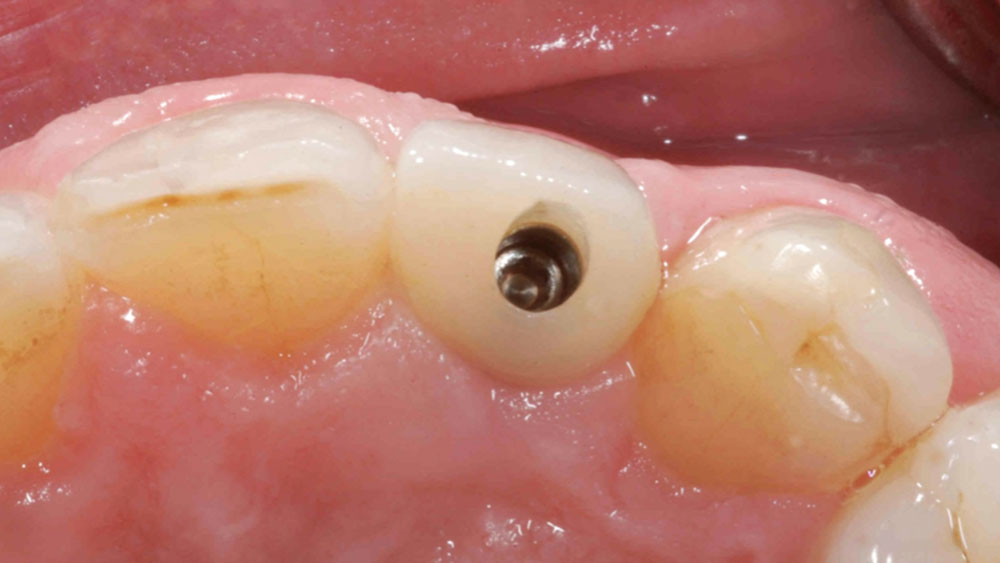

To achieve an optimal functional and esthetic outcome, the implant must be placed correctly with regard to trajectory, adjacent vital anatomy, and buccolingual, apicocoronal and mesial-distal positioning. Situating the implant so that the edges of the osteotomy are at least 2 mm from the buccal and lingual cortical plates, 2 mm from adjacent roots, 2 mm from vital structures, and 2–3 mm below the crest of tissue will keep the implant within the envelope of acceptability. The implant trajectory should emerge lingual to the incisal edge of the planned restoration, which allows for a screw-retained crown.

This case is an example of an ideal clinical situation for dentists who are new to placing implants in the esthetic zone. The patient requested treatment for a fractured upper lateral incisor. After extraction, grafting and healing, ample bone and soft tissue were present, and an implant was placed in optimal position for an esthetic result. The screw-retained restoration predictably restored form and function, illustrating the beautiful results that can be achieved by observing simple surgical and prosthetic guidelines.